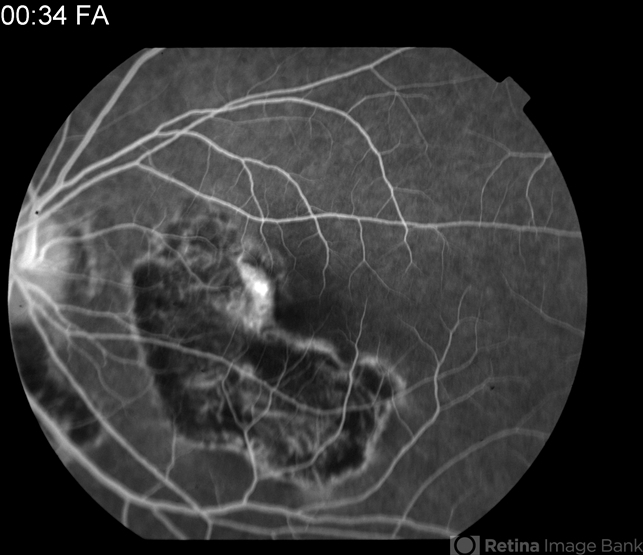

- macula serpiginous choroidopathy

- Tom Steele, CRA

Fundus camera

TRC 50ex - Description